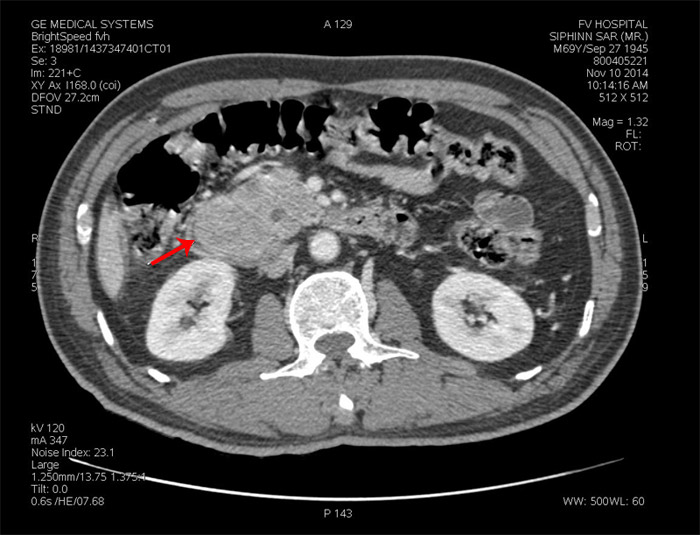

Bệnh nhân D, 69 tuổi, từ Campuchia sang Bệnh viện FV trong tình trạng ăn uống kém, sụt hơn 5 kg trong ba tháng. Sau khi khám lâm sàng, nội soi dạ dày – tá tràng, chụp CT scan…, bệnh nhân được xác định có khối u ác tính nằm ở đầu tụy, tại vùng hợp lưu ống tụy – ống mật – tá tràng. Bệnh nhân được mổ sớm nhất có thể để cắt bỏ triệt căn khối u.

Khối u đầu tụy (dấu mũi tên chỉ) của bệnh nhân D trên film CT scan)